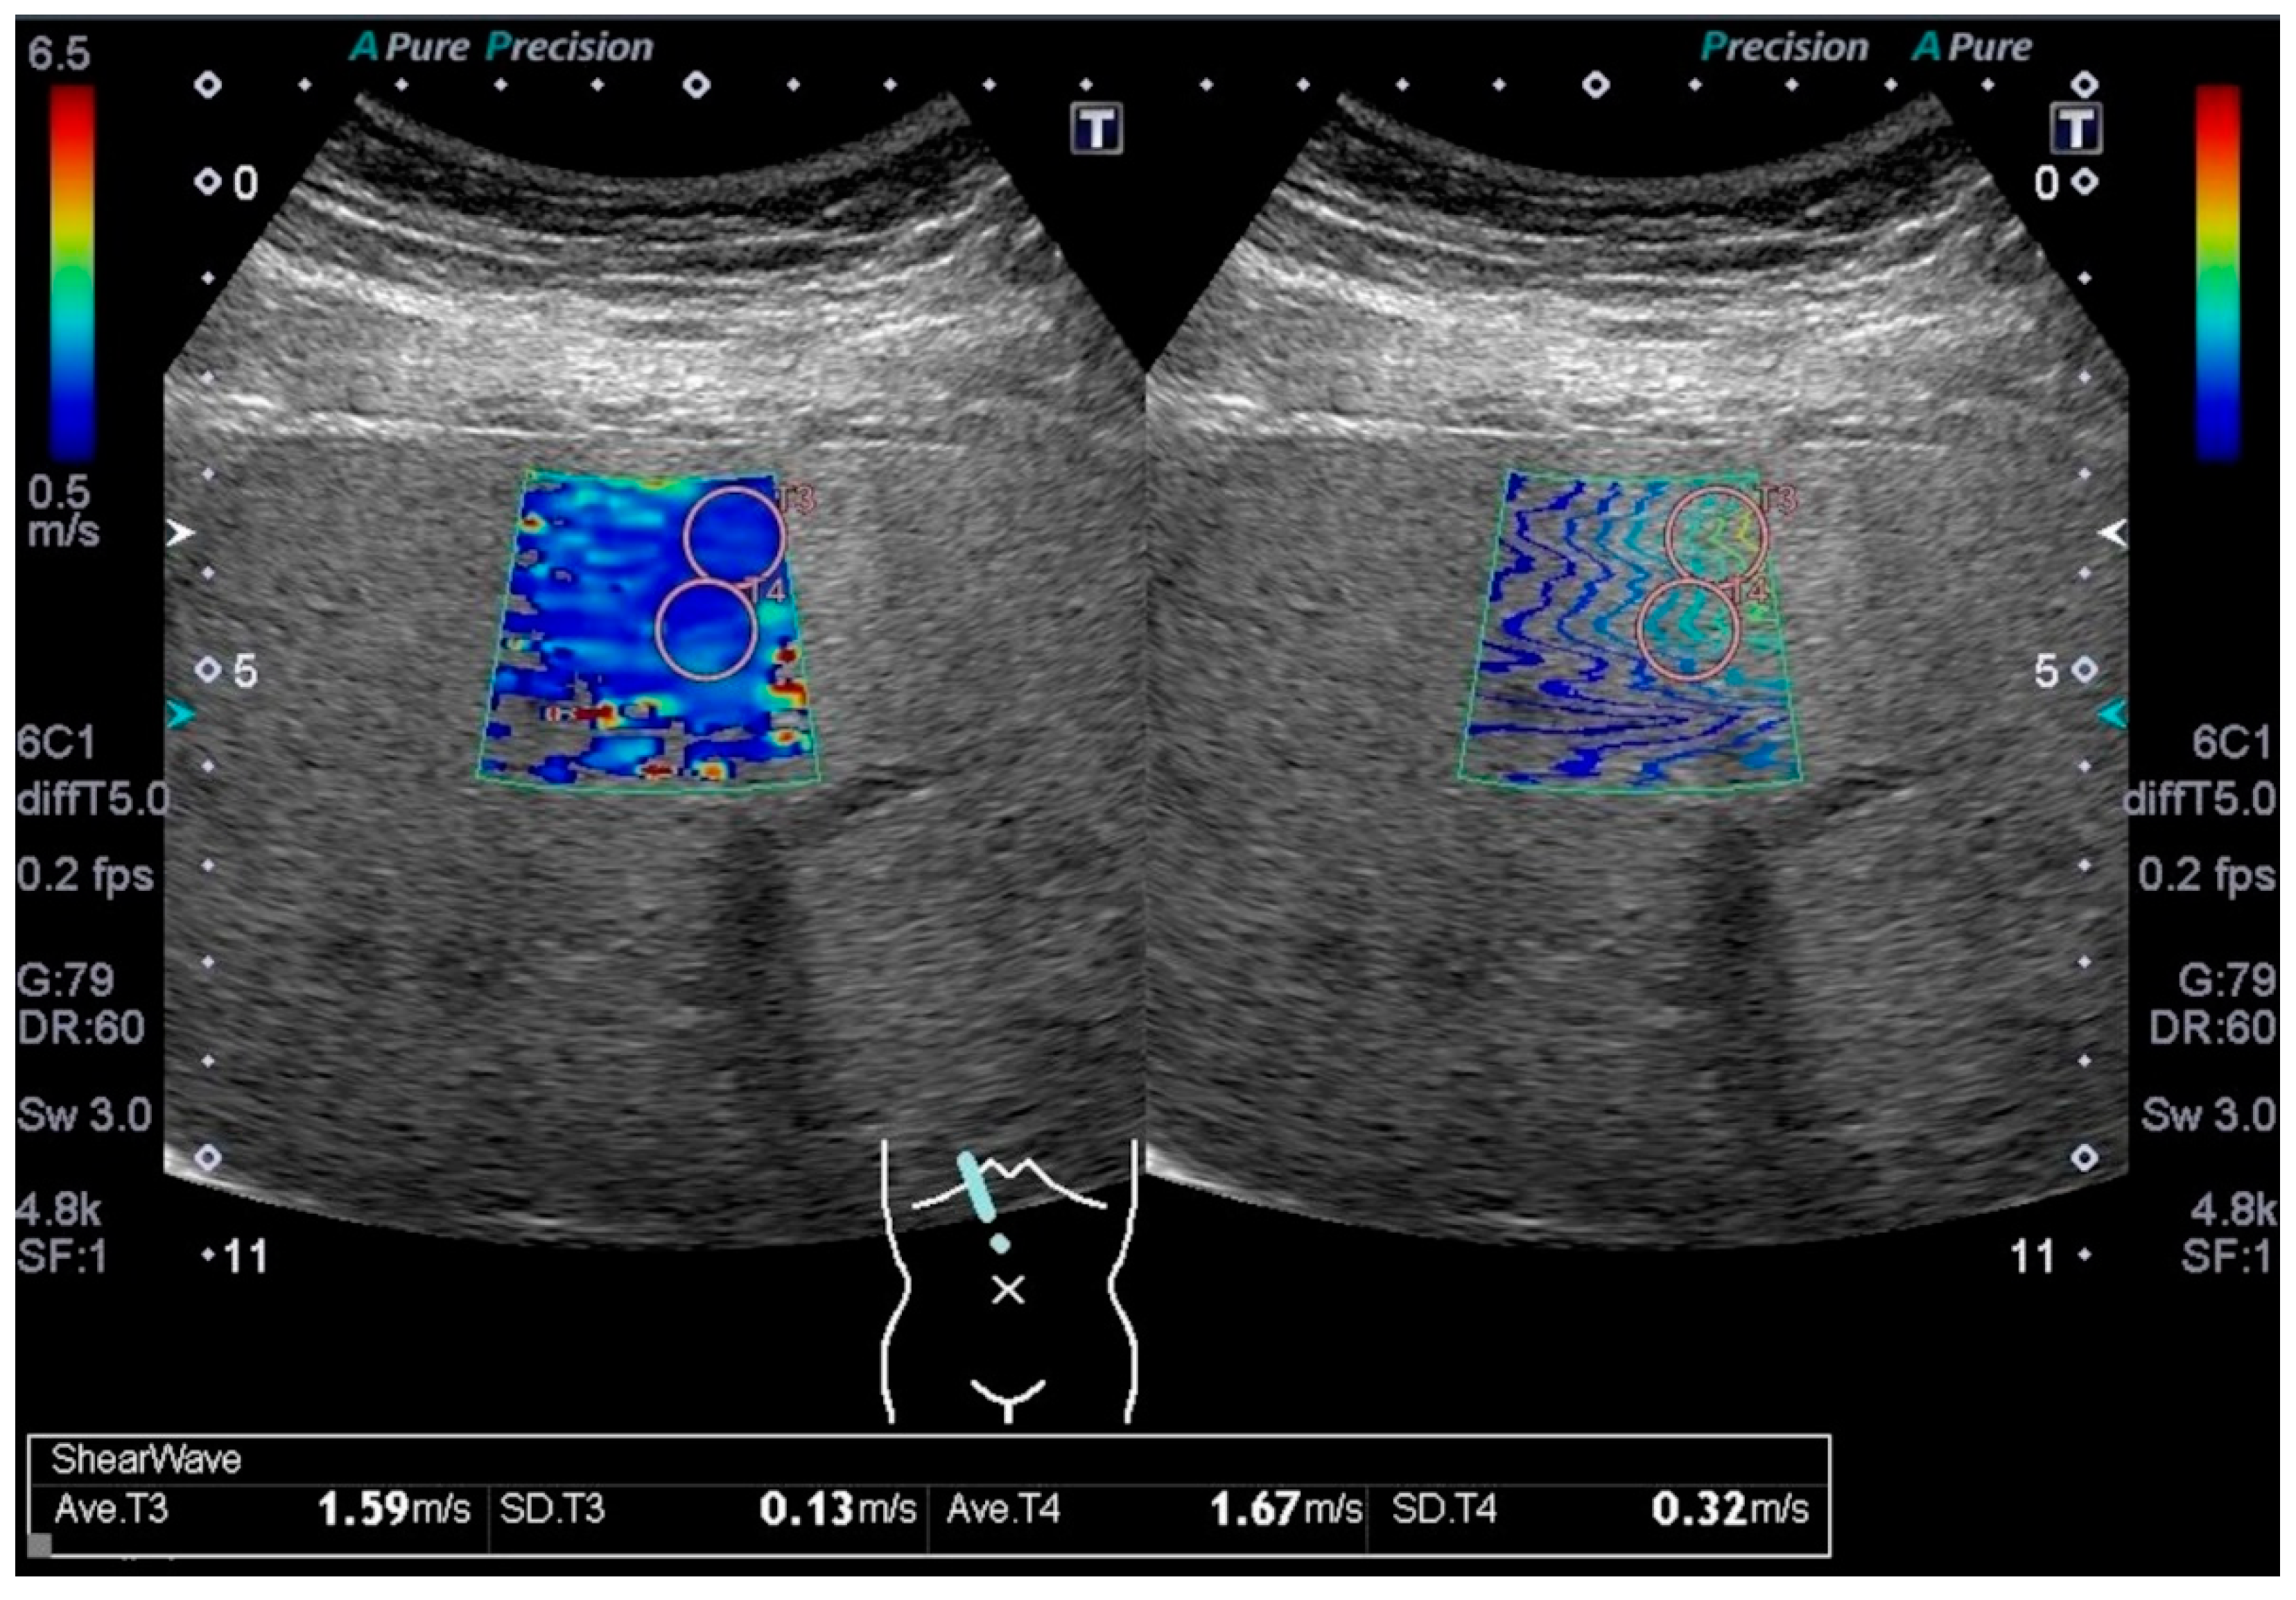

2.2. Data Collection and Measurement of Liver Stiffness